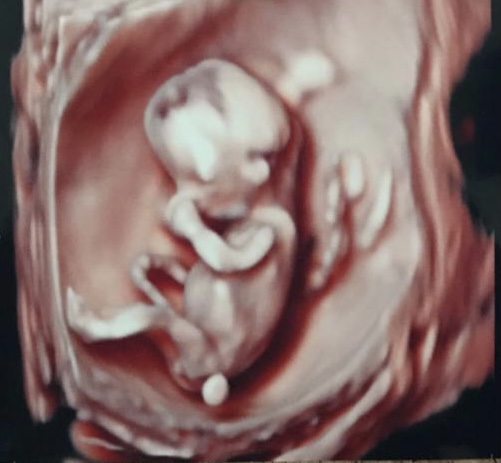

Holky, tak já jdu na utz nakonec už zítra, doktorka mě předobjednala 🙂 budu 7+6 podle ms, tak snad to nebude moc brzo...

Jinak jsem vlastně ráda, že ultrazvuk bude až v pátek. Holky, co myslíte, je možné už takhle brzo udělat utz přes břicho? Chtěla bych pokud možno těhotenství úplně bez vaginálních vyšetření. Max stěr na streptokoka před porodem. Určitě to budu řešit s doktorkou, ale zas se jí nechci ptát na úplnou blbost....